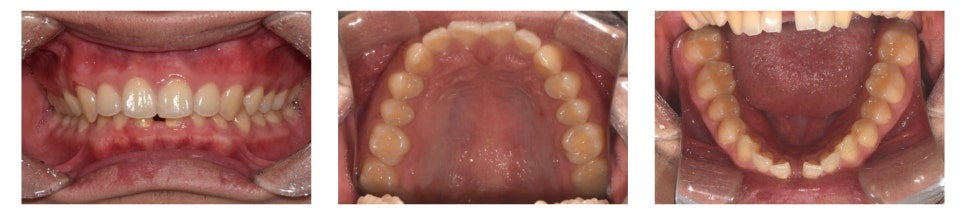

치료 시작 약 1년 4개월 후 치료를 완료하였습니다.

치료 전에는 눈에 띄게 벌어져 있던 하악 전치부의 공간(spacing)이 정상적으로 배열되었고, deep bite도 개선되어 기능적으로 안정된 교합을 얻을 수 있었습니다.

환자 또한 치료 결과에 매우 만족하였습니다.